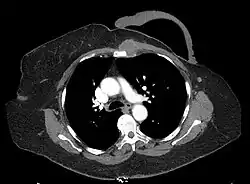

Internal Mammary

Left internal mammary node recurrence